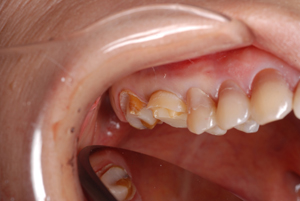

■口の中の金属を白くする症例

初診時